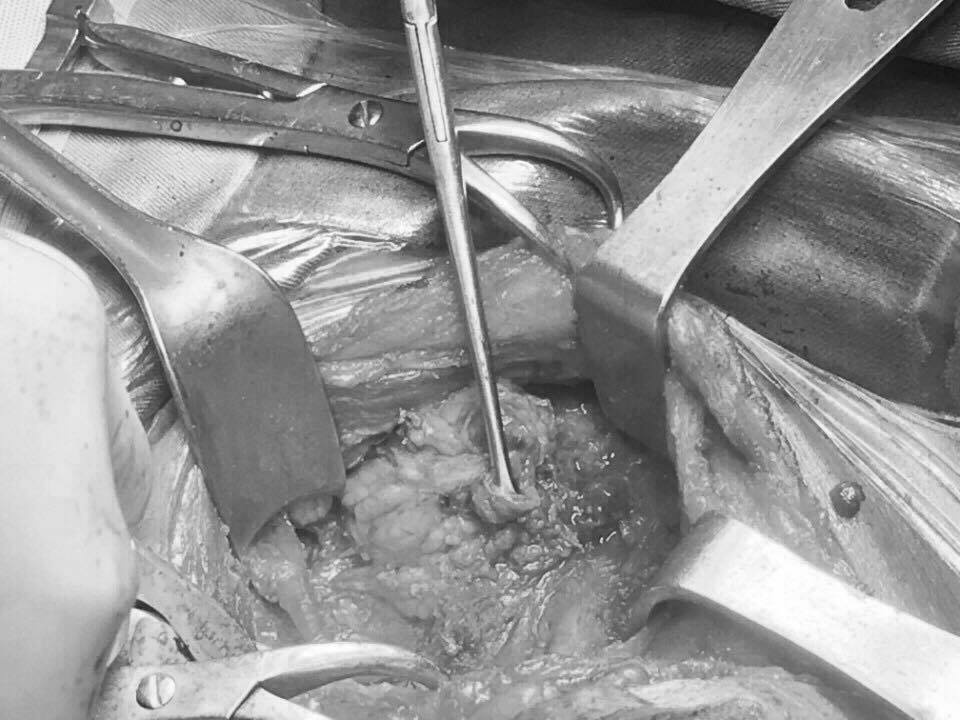

Sau khi làm các xét nghiệm, siêu âm, chụp cắt lớp, chọc tế bào kết quả cho thấy bà mắc ung thư tuyến giáp di căn hạch. Sau khi phẫu thuật các bác sĩ đã lấy được 8/16 hạch di căn.

| Sau khi phẫu thuật các bác sĩ đã lấy được 8/16 hạch di căn. Ảnh: T.Q. |